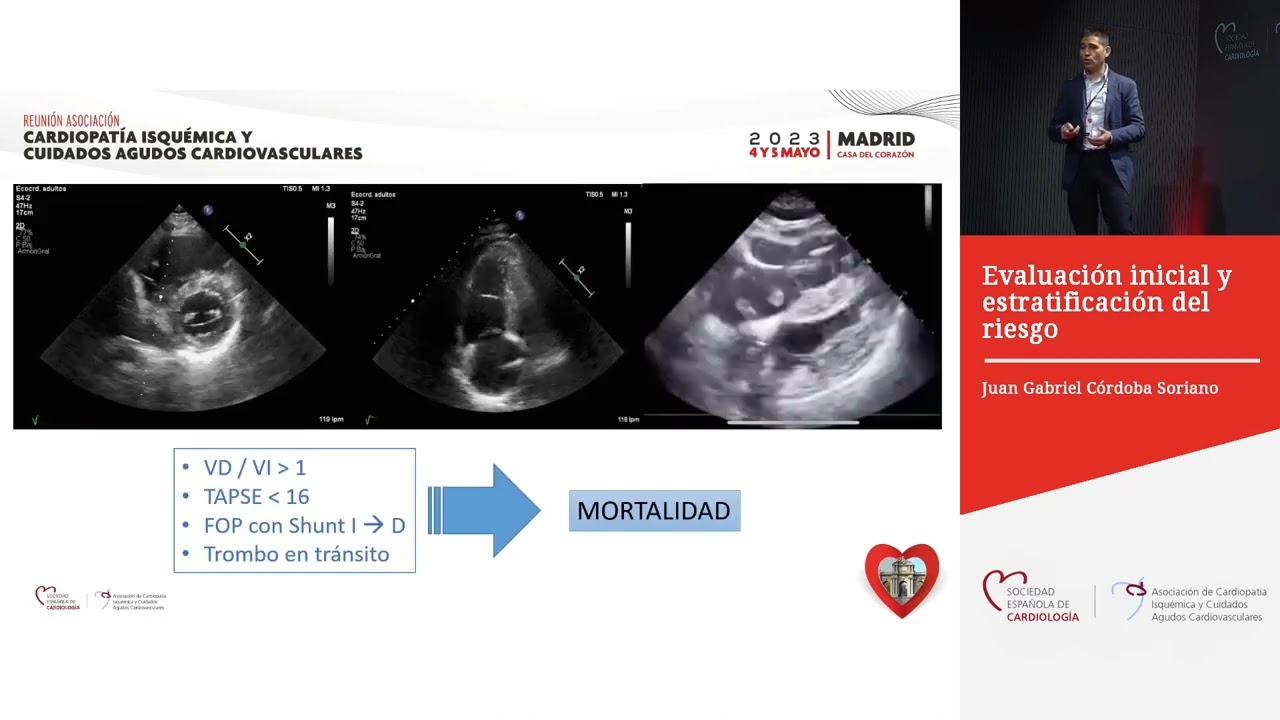

muchos líquidos pero no responde a los poquitos líquidos que le podemos poner al paciente si el paciente cumple con alguna condiciones de inestabilidad hemodinámica el paciente tiene un alto riesgo qué significa eso qué va a cambiar cómo Voy a abordarlo cuando yo tengo un paciente que me compra definición en esta demo dinámica esos criterios de wells que todos han escuchado no aplican no me va a poner a ver si tiene una alta probabilidad a una probabilidad intermedia una probabilidad baja no lo que yo voy a hacer es hacerle un ecocardiograma y si en el ecocardiograma

yo encuentro signos de disfunción ventricular derecha hago el diagnóstico y te dice la guía que si usted puede Hacerle la ingesta de una vez hágaselo pero pues seamos realistas por lo menos acá en colombia hacer una dieta que una va a depender mucho del sitio donde esté pero en la gran mayoría de los sitios no va a ser factible entonces si yo tengo un ecocardiograma y si en el ecocardiograma encuentro signos de disfunción ventricular derecha tiene diagnóstico de test y lo manejó como tal aquí no está en esta guía pero también está dentro no está

normal va a ser el país y clase 1 o país y clase 2 y el riesgo intermedio va a ser el país y clase 3 4 o 5 y con el peso simplificado simplemente va a ser ningún punto riesgo bajo un punto más riesgo intermedio hay Estudios de comparación y el pepsi simplificado es igual a utilizar el pepsi norma cuando el paciente tiene un riesgo intermedio se inventaron una nueva clasificación ya hace bastante que es el riesgo intermedio alto que es ese riesgo intermedio alto son pacientes con riesgo intermedio pero que están sobrecargando el ventrículo

derecho o sea no están inestables no es un riesgo alto pero si están sobrecargando el ventrículo Derecho y eso lo evidenciamos no sólo por el peso sino porque el paciente tiene un ecocardiograma con disfunción de ventrículo derecho y tiene elevación de troponinas ese es un riesgo intermedio alto si el paciente no cumple con eso sería un riesgo intermedio bajo y si por page y pues no lea es un riesgo bajo y si el país pues entonces sería un riesgo intermedio abajo porque se inventaron esto o sea porque Dijeron vengan hagamos un grupo de riesgo intermedio

alto la razón fue porque ser en cuenta que este grupo se moría más había una mayor mortalidad en este grupo y anteriormente sólo se hacía eco cardiograma al riesgo intermedio pero algo nuevo que tiene la guía europea es que a todo paciente contento hay que hacerle un ecocardiograma previo al egreso entonces dijeron venga pues si el grupo de riesgo intermedio alto se muere más Porque no los intentamos trombo lizar a ver qué pasa entonces se creó este estudio que es el pelito en el cual cayeron estos pacientes que tenían disfunción de ventrículo derecho biomarcadores positivos